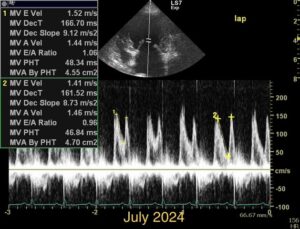

Chronic stage C MVD.TID Pimo and Lasix(high dose), ACEi and Spirono. Doing well. Recheck: Idexx GHP= CBC-NSF ,SDMA 15,BUN 14.1mmol/L, Creat 79umol/L. US: Cornell Indx LVd=1.46(prev2.1), LV septal flattening with diastolic dip,LAAO=2.47,Evel1.45m/s, TVregPG-68mmHg,HV distension-mod ascites.LV and LA underloading via diuretics and PHT (mild PHT past).PHT more pre vs post cap based on small LVsize? Consider Sildenafil/L Arg.Concerned about developing L CHF.Is CHF less likely adding PDE5i with MVD/PHT in underloaded LV than same scenario with vol overloaded LV at similar staging. MVPG=120.3mmHg

Dan, considering the LAE in addition to LV underloading – does this dog have mitral stenosis?? As you suggested, with this degree of LAE I would expect LVE as well….

Thanks. Not sure if any sig. MV stenosis?? My experience limited.3 PWD from diff times. Ls7 vid. is from 2024,initially thinking reverse remodelling where the lasix lowering preload and Pimo is decreasing LV size via decreased resist/increase cxn while LA no change because it’s a chronic filled remodeled saggy bag receiving Regurge volume??